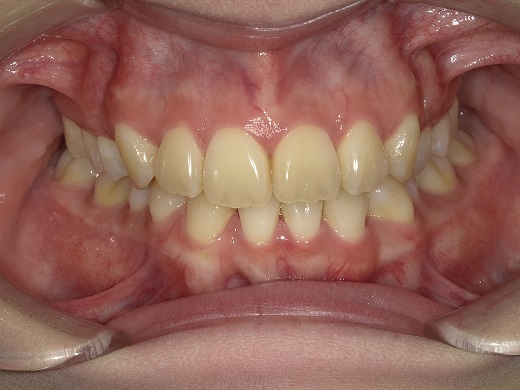

治療前正面

治療中正面

治療後正面